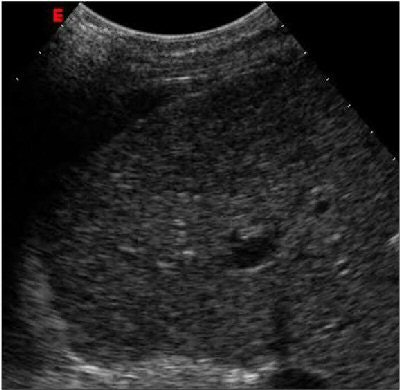

| Above: Ultrasound study of an early-stage hepatocellular carcinoma. At baseline examination, the lesion is iso-hypoechoic and hardly detectable. Below: After injection of the contrast agent SonoVue (Bracco), the tiny nodule clearly stands out against the surrounding liver parenchyma due to its arterial vascular supply. Images courtesy of Bracco and Dr. Riccardo Lencioni, University of Pisa, Italy. |